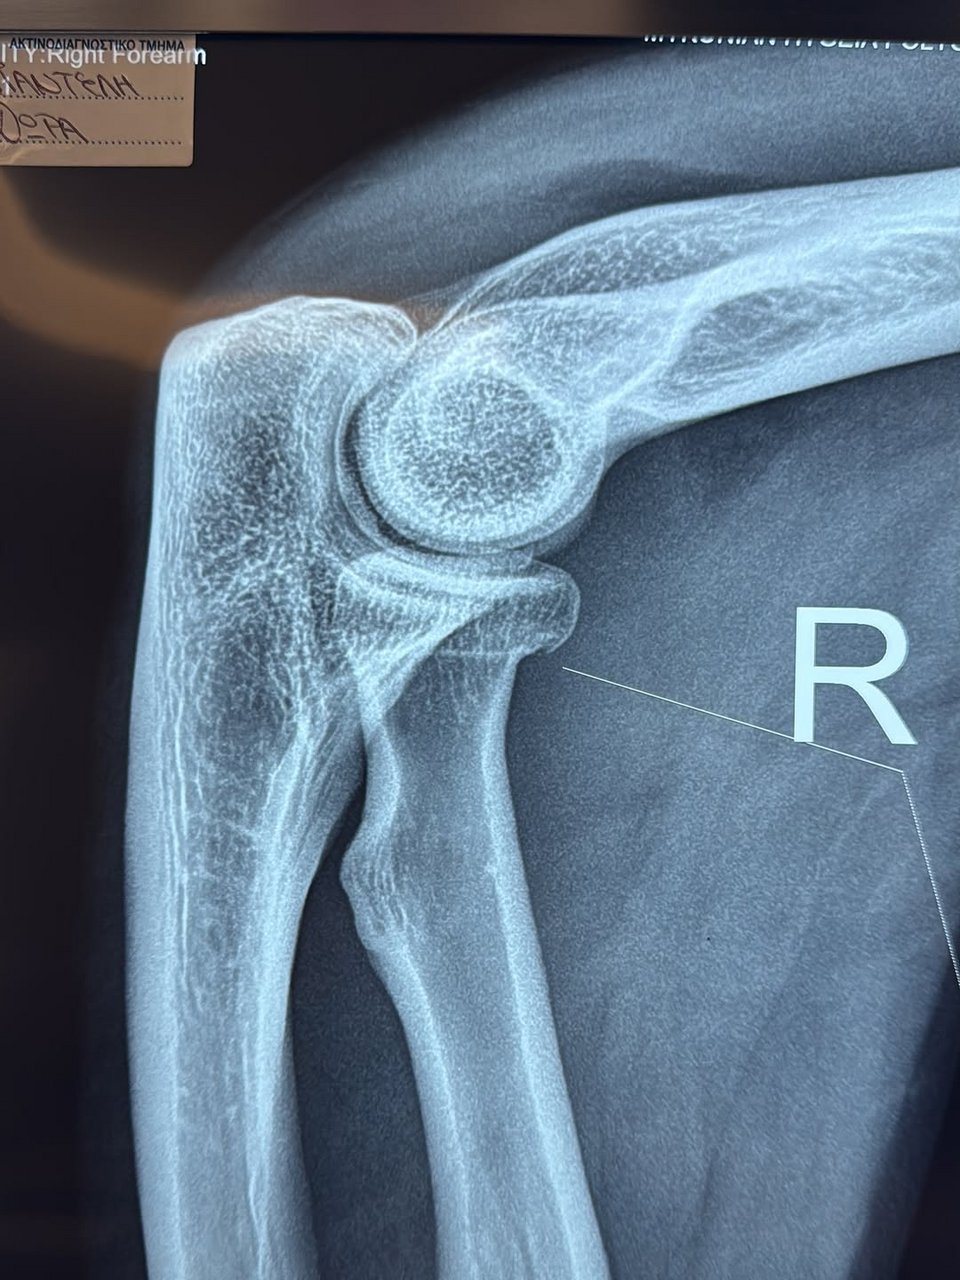

Υπέστη ρωγμώδες κάταγμα στο χέρι

Παρά τον τραυματισμό της, η ίδια διαβεβαίωσε πως τόσο εκείνη όσο και το μωρό της είναι καλά στην υγεία τους. Όπως εξήγησε, υπέστη ρωγμώδες κάταγμα στο χέρι, αιματώματα στον ώμο και τον αγκώνα, καθώς και μελανιές στο γόνατο. Για τον λόγο αυτό, αποφάσισε να επιστρέψει στην Αθήνα την επόμενη ημέρα ώστε να αναρρώσει στο σπίτι της.